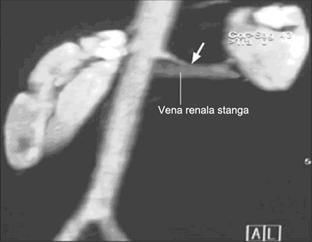

AngioCT tridimensionala (CTA 3D) asigura o modalitate rapida si noninvaziva de evaluare a elementelor vasculare din pediculul renal. Aceasta poate evidentia cu acuratete arterele si venele renale si se apropie de angiografia conventionala in depistarea majoritatii afectiunilor vasculare. Numarul, dimensiunea, traiectul si raporturile vaselor renale sunt usor de apreciat folosind aceasta editare interactiva a imaginilor in timp real.

Artere renale normale la un pacient de 44 de ani. A. imagine angioscopica sagitala care asigura o vedere dinauntru a aortei si evidentiaza clar ostiul renal (sageata) B. Imagine anterioara in care se observa ramificarea prepolara a arterei renale stangi (sageata).

Pentru evaluarea hilului renal, sunt folosite sectiuni sagitale, axiale, coronale. Imaginile in perspectiva permit utilizatorului sa vada in interiorul vasului, producand imagini angioscopice care sunt foarte utile in diagnosticarea stenozelor vasculare.

Angiografia computerizata tridimensionala poate determina cu mare rapiditate si precizie localizarea si traiectul vaselor renale. Vederea angioscopica asigura in plus informatii despre anatomia vasculara a rinichiului.

Clasic, ramurile arteriale sunt identificate cel putin pana la nivel segmentar. Limitarea vizualizarii acestora apare la vase cu dimensiuni mai mici de 2 mm. Sensibilitatea pentru evidentierea si localizarea arterelor renale principale este de aproape 100%. Descoperirile chirurgicale si cele computertomografice se suprapun in 95% din cazuri. Anatomia venoasa a rinichiului este de asemenea bine evidentiata prin aceasta metoda, fiind in mod deosebit de utila pentru pacientii care vor suferi o nefrectomie laparoscopica in scopul donarii de organ. In special anatomia rinichiului stang este foarte importanta, aceasta parte fiind preferata pentru donare. Tributarele venei renale, in special venele lombare posterioare, sunt evidentiate cu precizie si este de o mare importanta chirurgicala diagnosticarea unor dilatatii la nivelul lor.

De asemenea detectarea ramificarii prehilare a arterei renale, o varianta destul de comuna in populatia generala, este si ea importanta si necesara in evaluarea donatorilor de organ.